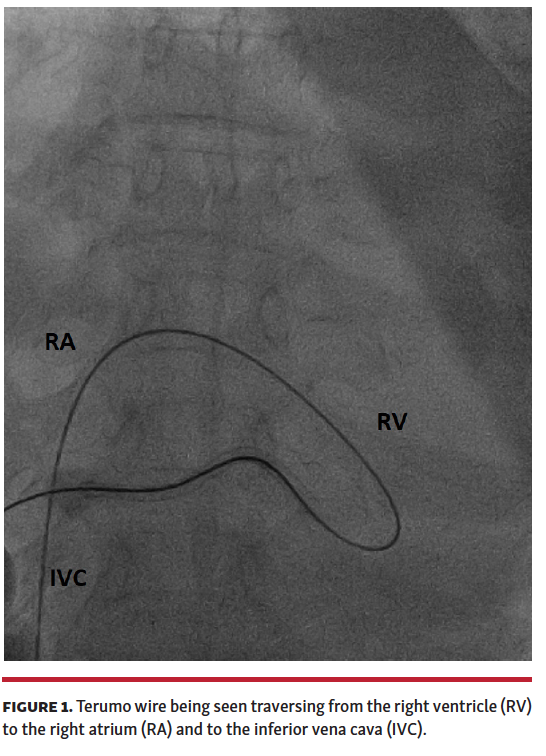

A 52-year-old woman presented to another hospital with progressive dyspnea of 10-day duration. The patient was diagnosed with a massive pericardial effusion and underwent pericardiocentesis. However, the patient’s symptoms did not improve and she was referred to our hospital with a pericardial sheath in situ. On evaluation, the patient had a large pericardial effusion and evidence of cardiac tamponade, but no fluid could be aspirated from the sheath. We attempted intrapericardial placement of a guidewire through the sheath to allow the insertion of a pigtail catheter. A 0.035˝ J-tipped Terumo wire was inserted, and it coursed through the right ventricle into the right atrium and inferior vena cava (Figure 1). Angiogram (Video 1) showed the sheath to be communicating with a tributary of the middle cardiac vein with contrast opacification of the coronary sinus and right atrium (Figure 2), and spillage of dye into the pericardium. The patient underwent surgical exploration. The sheath was inside the pericardial cavity; however, no damage was observed to the right ventricle or coronary venous system. The exact communication could not be documented as the sheath was likely pulled into the pericardial space during manipulation. The guidewire likely passed through one of the tributaries of the middle cardiac vein connected to the thebesian veins that drained directly into the right ventricle, as can be seen from the course of the wire (Figure 1). The patient was diagnosed to have pericardial tuberculosis and treated with antitubercular therapy. She was discharged and is doing well on follow-up. The current case underscores the importance of image-guided pericardiocentesis.